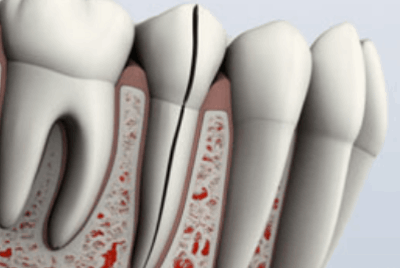

Diente partido:

Un diente partido suele ser el resultado de un diente fisurado no tratado. Se puede identificar por una grieta con segmentos distintos. Este tipo de diente nunca se puede salvar intacto. Sin embargo, la posición y el alcance del problema determinarán si se puede salvar alguna parte del diente. A veces, el tratamiento endodóntico y la restauración por parte de su dentista se pueden salvar una porción del diente.